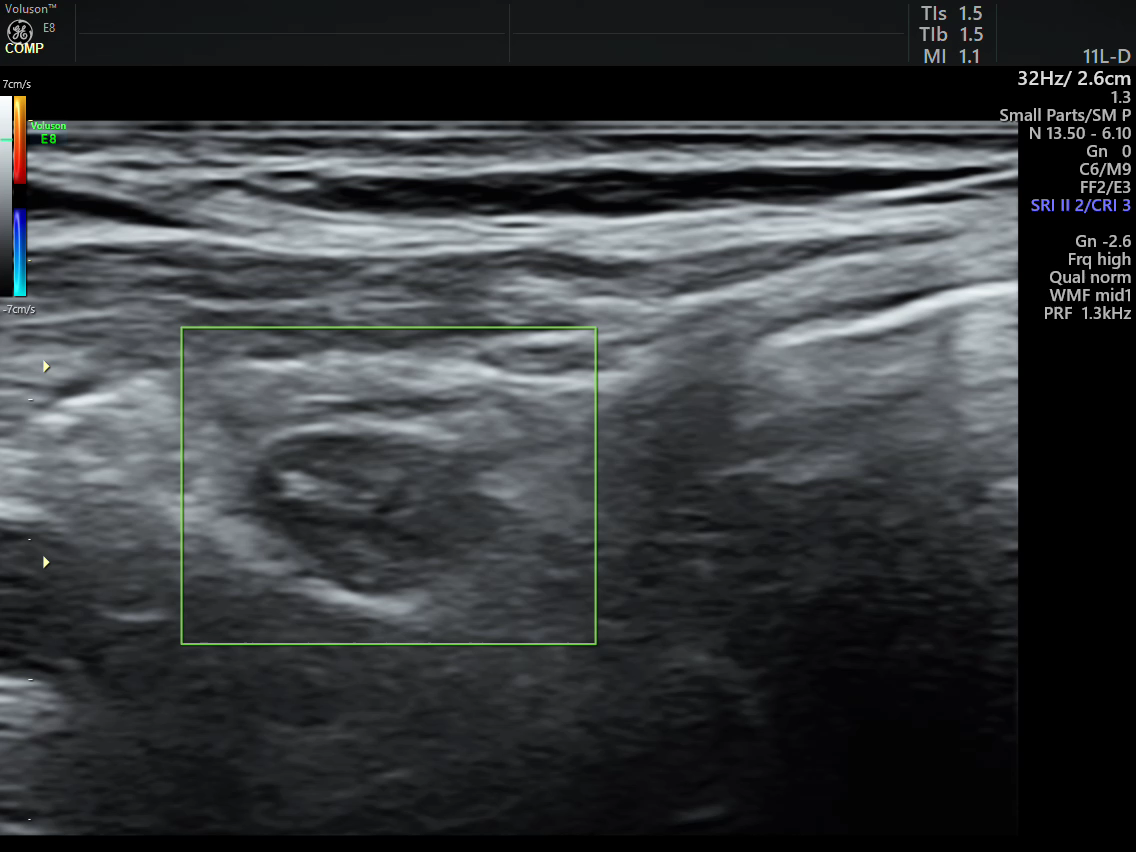

该患者为年轻男性,因当地体检发现骨密度减低,随即到西安、北京多家大型三甲医院复查,发现甲状旁腺激素及血钙水平异常升高,超声检查提示左侧甲状旁腺占位。因多方了解我院超声医学科可以射频消融治疗,为求精准诊治慕名前往我院陆港院区超声医学科求治。我科魏炜副主任在详细了解该患者既往临床资料后对其进行了超声检查,发现该患者左侧下部甲状旁腺内可见一大小5.1x5.2x13.2mm低回声结节,边界清,形态规则,内回声欠均匀,CDFI:结节内部可见丰富血流信号;余甲状旁腺形态、大小未见异常。患者甲状旁腺素158pg/ml(正常参考范围15-65pg/mL),血钙2.89mmol/L(正常参考范围2.11—2.52mmol/L),魏炜副教授根据该患者超声图像特征结合实验室检查明确诊断该患者为原发性左侧下部甲状旁腺功能亢进(甲状旁腺腺瘤),符合射频消融指征。魏炜副主任为患者详细讲解了治疗目的、步骤及可能发生的并发症后,患者决定采取该微创治疗方式。在日间诊疗中心的支持下,患者顺利住院并完善术前检查。

治疗前病灶血流丰富 治疗后病灶血流消失